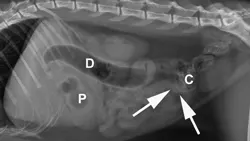

A) Right radiograph, B) Left radiograph, and C) Ventrodorsal radiograph

Abdominal radiography: Left/right lateral and VD views.

Radiographic Findings: The stomach (St) and duodenum (D) are severely distended with fluid and gas, suggesting intestinal obstruction or possibly pancreatitis with secondary ileus.

There is a 1.5-cm rounded opaque structure (arrows) in the caudal abdomen, to the left of the descending colon on the VD view. It is partially obscured by feces in the colon (C) on the left lateral view. The remaining organs and serosal detail appear normal.

Comments: We often perform left and right lateral radiographic views of the abdomen in cases of suspected GI foreign bodies and obstructions since the fluid and gas disperse into different portions of the GI tract. For example, any gas in the stomach rises to the pylorus (P) in left lateral recumbency and may outline a foreign body anchored to this region; this is particularly useful in suspected linear foreign bodies, which typically anchor to the tongue or pylorus and subsequently plicate varying degrees of small intestine.